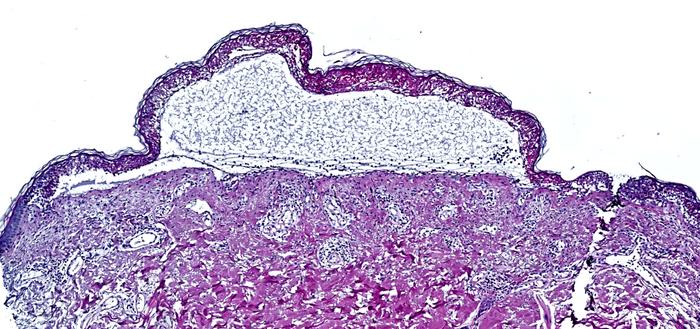

The researchers used spatial proteomics to analyze skin samples from patients with toxic epidermal necrolysis. This cutting-edge approach, known as Deep Visual Proteomics, merges powerful microscopy with AI-driven analysis, laser-guided microdissection and ultimately ultra-high sensitivity mass spectrometry. They zoomed in on individual cells and studied them like never before, creating a map of the thousands of proteins driving this deadly reaction.

Toxic epidermal necrolysis is a rare but extremely severe adverse reaction to common medications, such as allopurinol (which is used to treat gout) or certain antibiotics. It causes widespread blistering and detachment of the skin. With a mortality rate of up to 30 percent, it rapidly transforms from a seemingly harmless rash into a life-threatening condition. Until now, no effective therapy existed, with treatment primarily limited to supportive care.